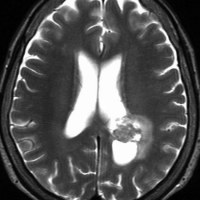

高齢者の無症候例です

60代の女性に無症候で発見された稀な部位のPXA。結節様ですが脳とのはっきりした境はなく,多房性ののう胞を伴っていました。T2とFLAIR像ではわずかな浸潤像あるいは腫瘍周辺浮腫が疑われます。PXAに特徴的な画像ですが,大脳深部発生でもあり,PXAと画像診断することはできません。定位脳生検術 MRI-guided sterotactic biopsyで病理組織診断を行ない経過観察しました。

3年観察したら嚢胞を伴って増大しました。幸いのう胞性拡大が脳表方向であったのでparietal transcortical approachで全摘出できました。側脳室三角部腫瘍への到達法と同じアプローチですが,この経路では頭頂葉症候を後遺することがありません。

術後は無症状で8年間再発はありません。